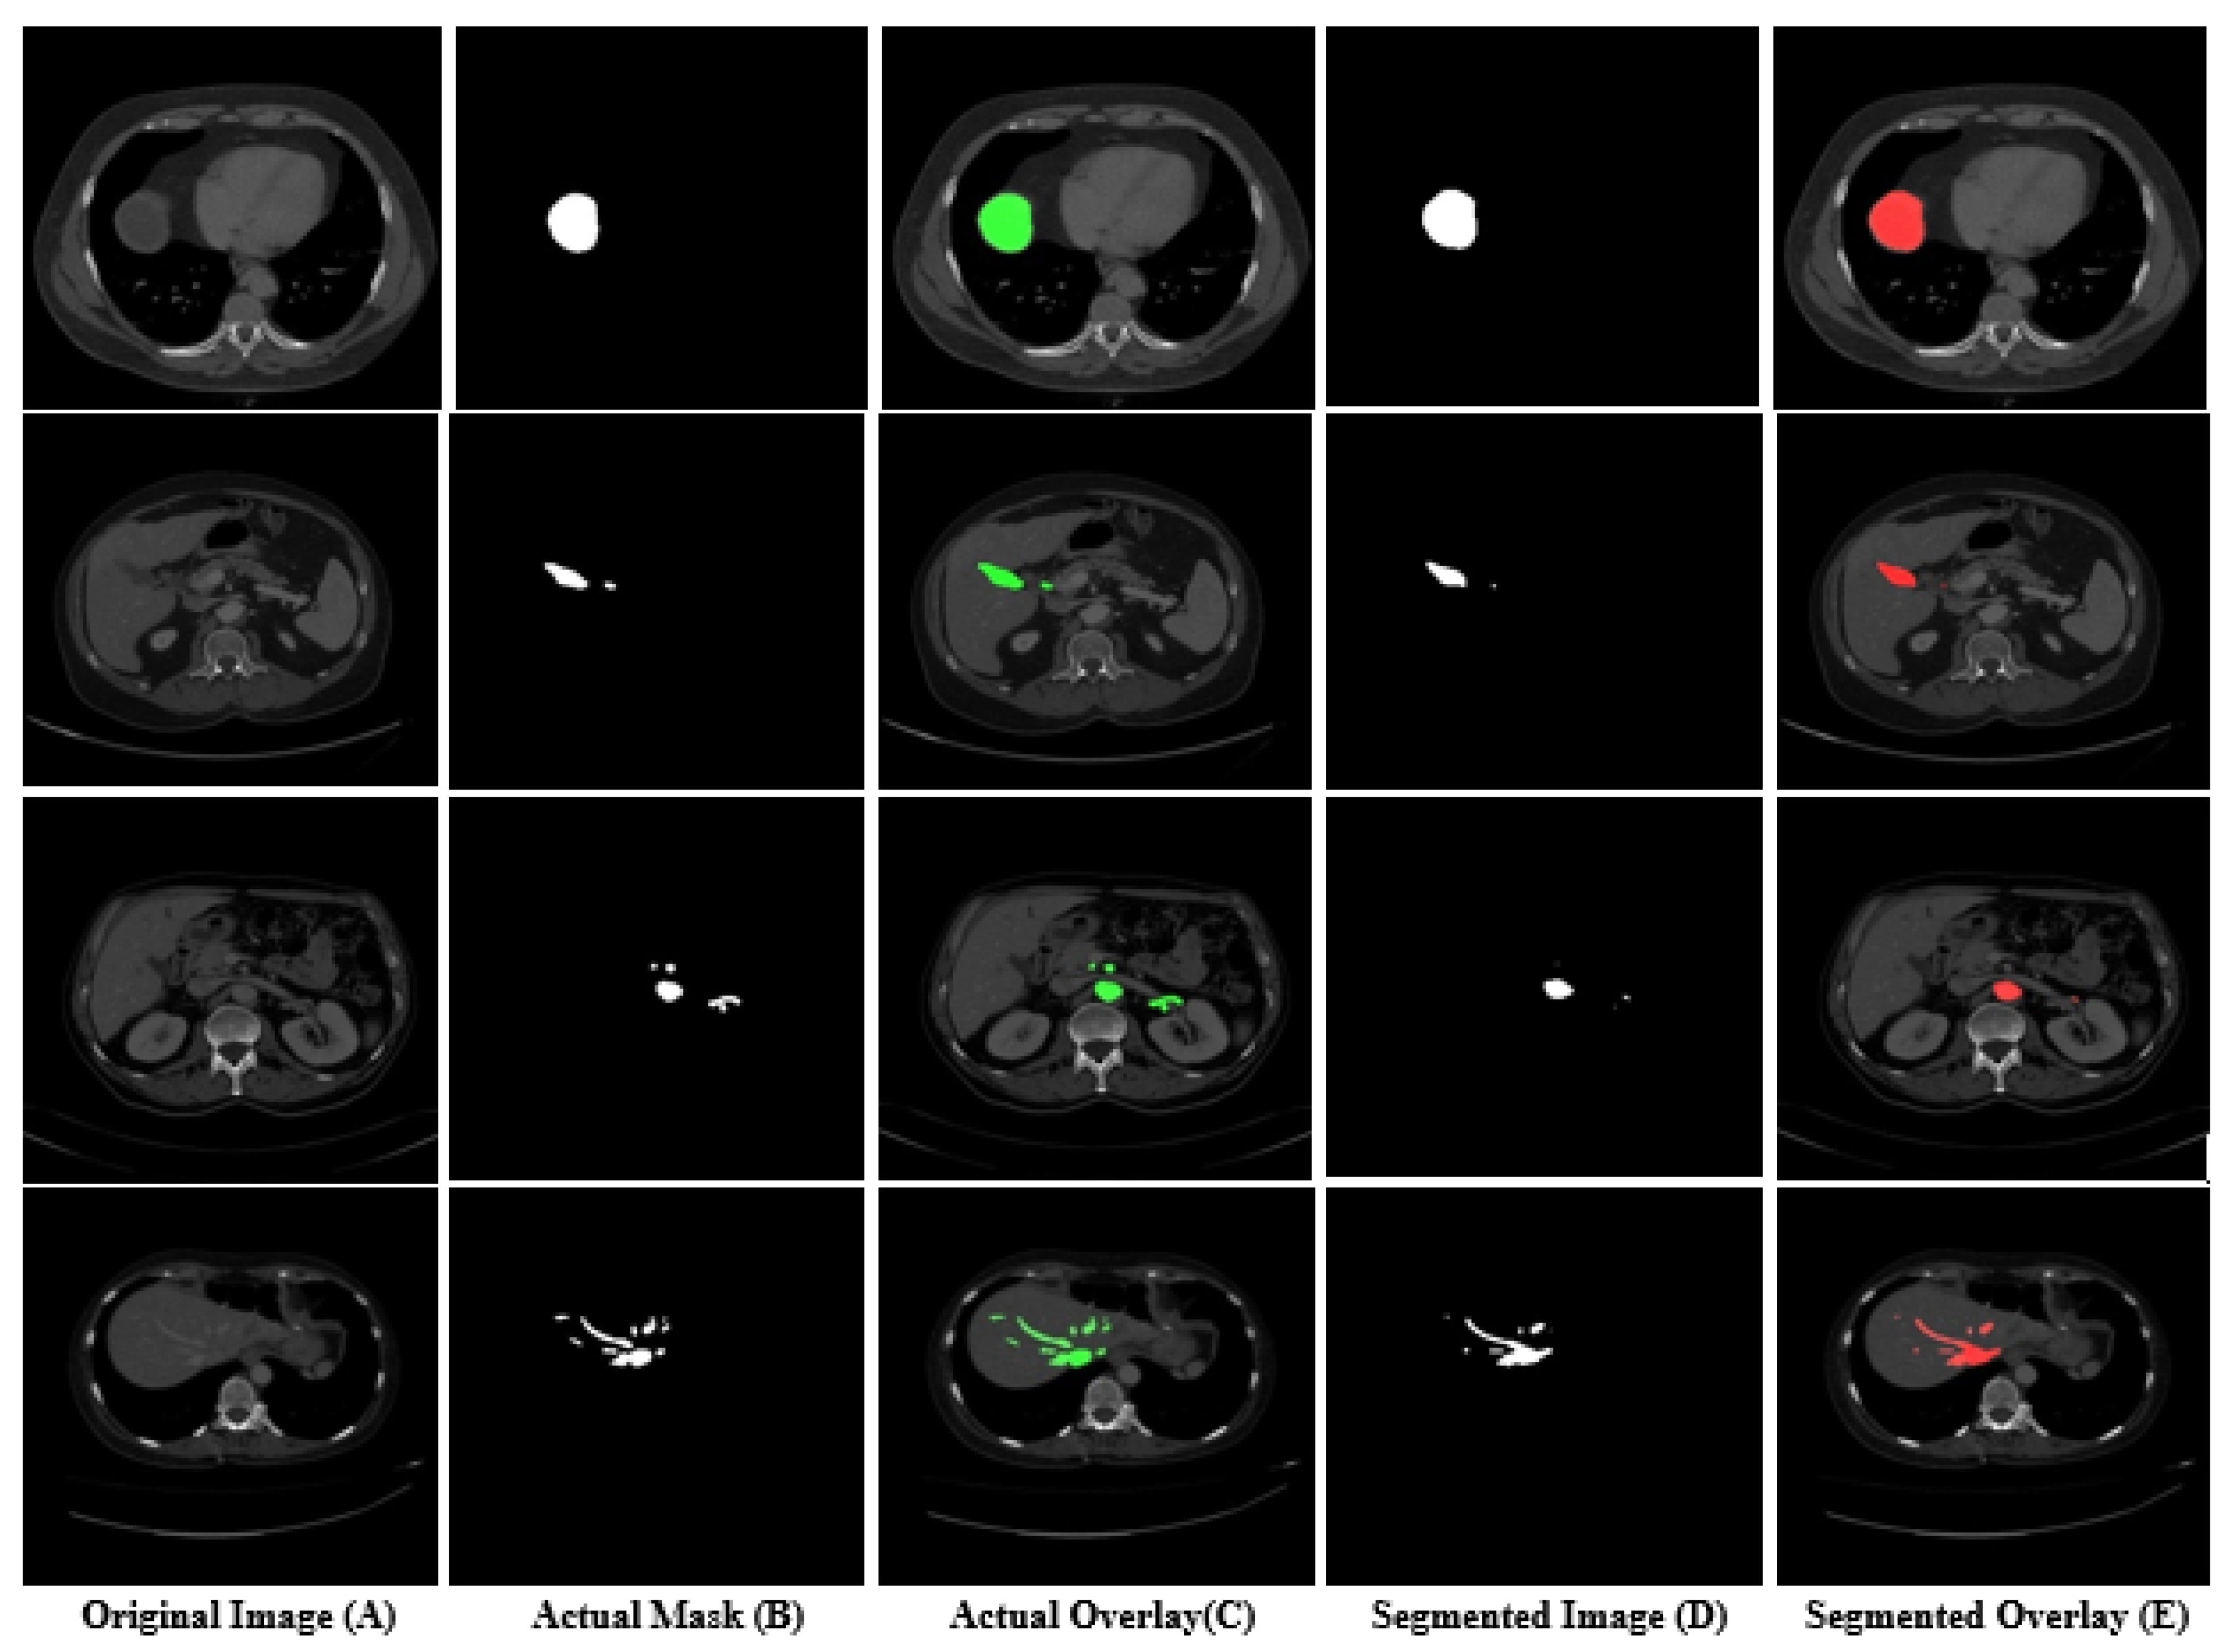

Moreover, some sample images that were segmented by our model are shown in Figure 6. In Figure 6, column (A) shows the original test set slice images, column (B) shows the actual masks of the tumor, column (C) shows the actual overlay results of the original mask over the image, column (D) shows the masks that were predicted by the model, while column (E) shows the predicted overlay results of a predicted mask on the images. It is observed from Figure 6 that the model found difficulty in segmenting very small tumors, as shown in the last row images. Similarly, the model also found difficulty in segmenting in the second row, as shown in columns (B) and (D) of Figure 6. All the scores were calculated with the help of predicted and actual masks, which are shown in columns (B) and (D) of Figure 6. Furthermore, the Dice and Jaccard scores of individual CT scan slices in the test set is shown in Figure 7. In Figure 7, the x-axis shows the number of CT scan slices, while the y-axis shows the dice and Jaccard score. It is observed from Figure 7 that, for most CT scans, the Dice score was above 80.

Figure 6.

Segmentation results of liver tumor from a CT scan using our proposed framework.